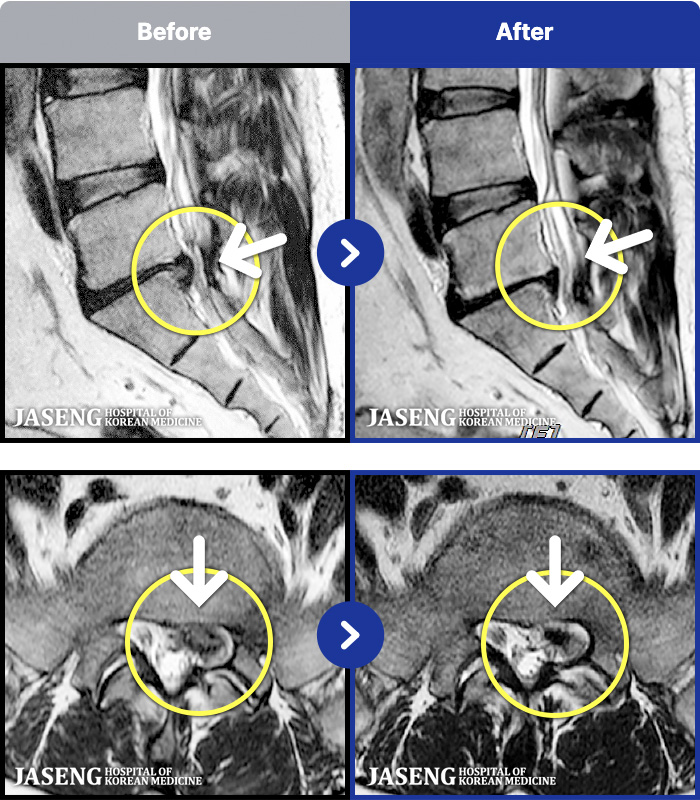

- MRI ġ

MRI ġ

191 MRI ũ ʸ Ȯϼ.

[_㸮ũ] ٸ 㸮 ȹٷ , Բ 㸮 ־ ߴ.